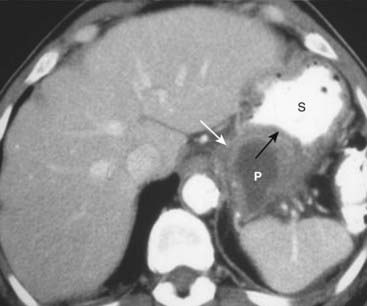

image

Figure 18-24 Pancreatic pseudocyst.

Pseudocysts (P) of the pancreas occur when fibrous tissue encapsulates a walled-off collection of pancreatic juices released from the inflamed pancreas. Pseudocysts may have an enhancing wall (solid white arrow). The cyst is indenting a loop of adjacent bowel, in this case the posterior wall of the stomach (S). The indentation on a loop of bowel by an extrinsic mass is called a pad sign (solid black arrow).